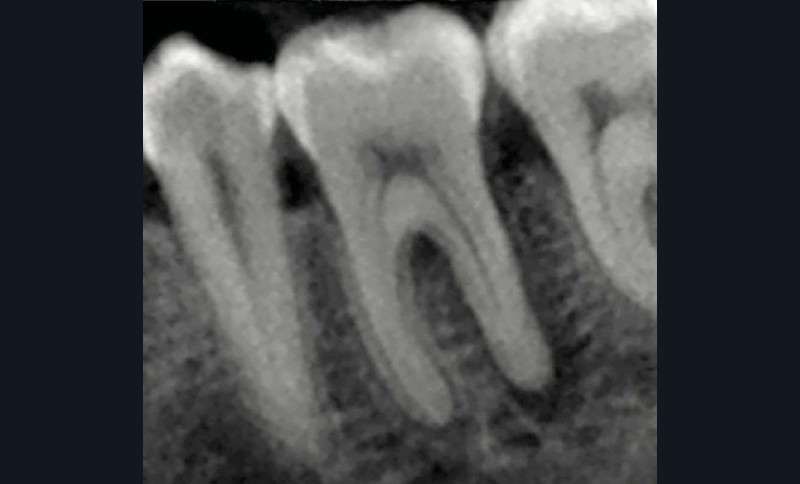

La compréhension de ces instruments, des biomatériaux et des différentes techniques est essentielle, et doit nous guider dans nos prises de décision en fonction des situations cliniques. Dans le cas clinique présent, suivi sur 24 mois, le patient se présente avec des douleurs à la mastication sur la dent 36. Tous les signes cliniques (test au froid négatif, test à la percussion positif, sondage parodontal positif en vestibulo-distal avec présence de fistule) et les examens radiologiques (LIPOE sur la racine distale, lésion inter-radiculaire) convergent vers un diagnostic de nécrose pulpaire due à une fracture longitudinale non complète (type 3 : Classification AAD) [1] (fig. 1).